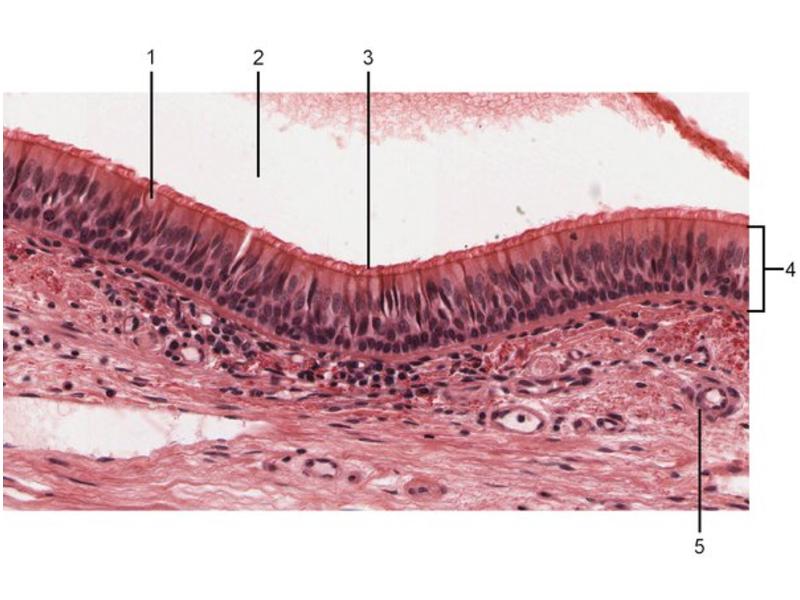

Slides: Respiratory System

- Slide 73: Trachea

Nostril

Respiratory epithelium

- Pseudostratified

- Ciliated

- Columnar

- Epithelium with

- 4 Cells

- Ciliated columnar cells

- Non-ciliated columnar cells

- Goblet cells

- Basal cells

Trachea